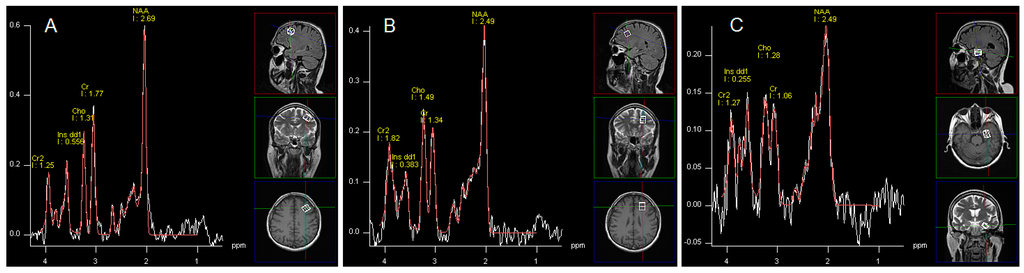

1H-MRS data were acquired by single voxel spectroscopy (SVS) using a point resolved spin echo (PRESS) sequence 128 averages; TR, 3000 ms; TE = 30 ms; voxel size was 15 × 15 × 15 mm for the left DLPFC, the left frontal WM and 10 × 15 × 20 mm for the left hippocampus. Regions of interest were placed in: the left DLPFC, left frontal WM and left hippocampus by a neuroradiologist (Figure 1). Automated procedures were used to optimize radiofrequency pulse power, field homogeneity, and water suppression, as well as to convert the lines into a Gaussian shape. Post-processing of spectroscopy data was performed by means of Avanto Syngo MR Software (Siemens, Munich, Germany), Level B15. It included: k-space Fourier transformation and a spatial 50 Hz Hanning filter; subtraction of the residual water signal; time domain 1 Hz exponential apodization; zero filling to 2048 points; Fourier transformation of the time domain signals; frequency shift correction, phase correction, and baseline correction. In postprocessing software also provided information about fitting error (deviation between theoretical and measured spectrum determined using the last squares method). We assumed that only spectra with fitting error less than 0.5 would be considered in the analysis. If the error was higher, the sequence was repeated. Hence, in all patients we received satisfactory values (mean fitting error 0.27 SD 0.12). The following metabolites were assessed: N-acetylaspartate (NAA); glutamine, glutamate and partially GABA (Glx); myo-inositol (mI); choline-containing compounds (Cho); creatine plus phosphocreatine (Cr). No absolute concentrations of metabolites were determined, but ratios to Cr and Cho.

Figure 1. Images showing voxel location in the left DLPFC area (A), left frontal WM (B), left (C) and an examples before (white line) and after (red line) fitting. Peak areas for N-acetylaspartate (NAA); creatine (Cr and Cr2); choline (Cho); and myo-inositol (mI dd1) are labelled.